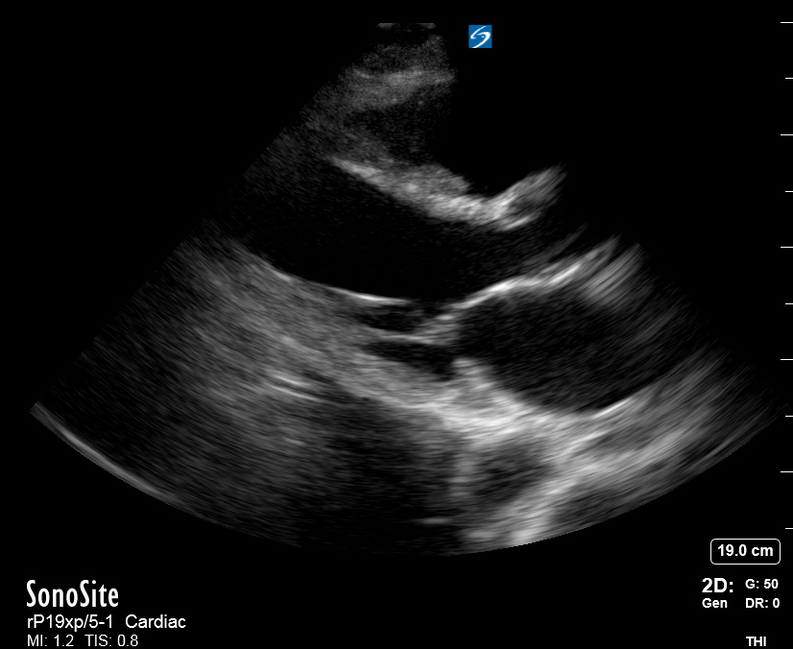

Ejection: is the LV dilated or significantly impaired?

THE VIEWS

The PLAX view is versatile and allows the recognition of multiple landmarks, making it good for visual estimation of LV contractility. It is essential to optimize the view ensuring a true sagittal long axis, as being oblique to the LV chamber may underestimate its size and overestimate its emptying. The PSAX view at the level of the papillary muscles reveals the entire muscular circumference and concentric squeeze of the LV. It is useful to estimate both global function and focal wall motion abnormalities. The A4C view, although technically challenging, provides good insight into the global myocardial function and chamber size.

LV CONTRACTILITY

Qualitative assessment of the LV and visual estimation of Ejection Fraction is based on three parameters:

Endocardial excursion.

Myocardial thickening.

Movement of the anterior leaflet of the mitral valve.

A qualitative assessment is typically categorised as:

Normal (LVEF 50-65%)

Moderately Depressed (LVEF 30-50%)

Severely Depressed (LVEF < 30%)

Hyperdynamic (LVEF > 65%)

SIGNIFICANTLY IMPAIRED / DILATED LV

A severely depressed LV contractility, particularly when paired with a plethoric IVC or lung B-lines, indicates systolic heart failure. Chronically raised afterload can lead to severe dilation of the LV.

HYPERDYNAMIC

In contrast, hyperdynamic states are associated with decreased afterload and are classically found in patients with sepsis or severe hypovolaemia. A hyperdynamic heart should be accompanied by a small, collapsing IVC. Moreover, is essential to remember that tachycardic is not the same as hyperdynamic, as the latter is a measure of contractile activity and emptying. A tachycardic heart is not necessarily hyperdynamic.